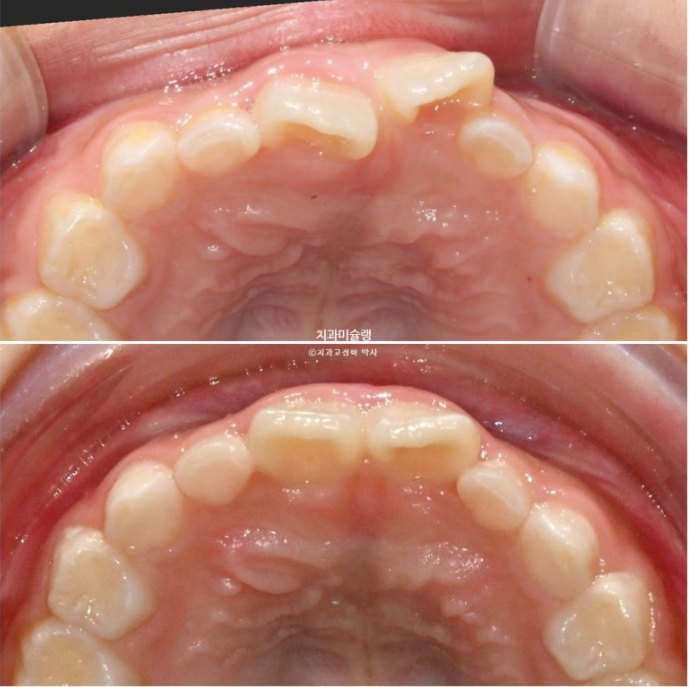

앞니가 거꾸로 물려서 온 7세 어린이 입니다.

윗니가 전체적으로 아랫니와 거꾸로 물리는 반대교합 입니다.

공간부족으로 앞니가 덧니처럼 나왔습니다.

두달 후 앞니 반대교합이 해소가 되어 왔습니다.

25.06

덧니처럼 배열에서 벗어나있던 앞니가 꽤 제자리로 들어온 것이 보이죠?

배열에서 벗어나있던 앞니가 3개월 전에 비해 좀 더 가지런하게 배열이 되어있습니다.

전 후 비교 보겠습니다.

25.04~25.09